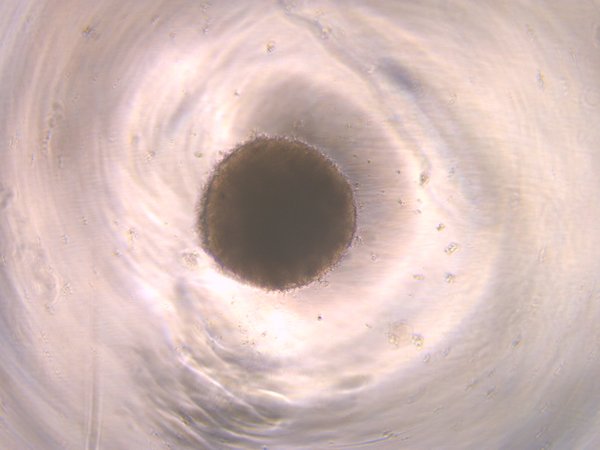

Wildtype (wt2D)

wt2D

Healthy control, Day 10